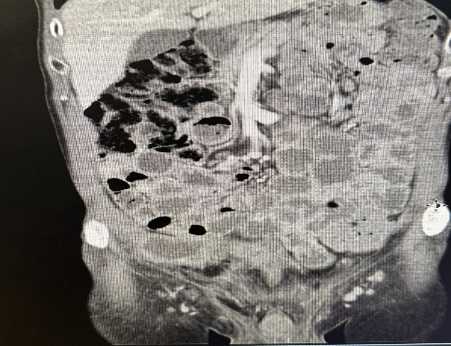

A 70-year-old male with a history of ischemic heart disease managed with a proximal LAD stent, and ongoing treatment with aspirin, atorvastatin, candesartan, and lansoprazole, underwent elective laparoscopic totally extraperitoneal (TEP) right inguinal hernia repair. The procedure was initially uncomplicated. Three years later, he presented with visible haematuria and right-sided abdominal pain. Cystoscopy revealed a 5 mm lesion on the right anterior bladder wall with floating debris, and although imaging excluded urinary obstruction, bowel inflammation raised concerns for possible Crohn’s disease (no previous evidence). The lesion was deemed benign, and he was referred to surgery for evaluation of groin discomfort. Shortly thereafter, he developed a right groin abscess, confirmed on CT and managed twice with ultrasound-guided drainage by interventional radiologist and antibiotics. However, symptoms recurred with ongoing purulent discharge from the suprapubic region. Further imaging revealed displaced mesh embedded within a heterogeneous collection. The patient remained systemically well but required readmission due to persistent wound drainage. A repeat CT (Figure 1) scan showed inflammatory collections in both the inguinal and pelvic regions, with compression of the urinary bladder and associated soft tissue changes. Urgent operative exploration revealed a chronic abscess cavity communicating with the mesh site; the mesh was partially floating and surrounded by infected granulation tissue. The sinus tract was excised, the cavity debrided, and the mesh removed (Figure 2). Postoperatively, the patient developed high-volume serous fluid output through the wound. An urgent cystogram was requested by the urology team after the referral confirmed a vesico-cutaneous fistula originating from the bladder base and tracking to the suprapubic wound (Figure 3). Conservative management with an indwelling urinary catheter was initiated with the urology team’s advice. Despite intermittent haematuria and cloudy discharge, the patient remained clinically stable and was managed with antibiotics. On follow-up cystography, no further leakage was observed, and the fistula was deemed healed, though mild left-sided ureteric reflux persisted (Figure 3). The patient was scheduled for uroflowmetry, and a bladder scan to assess function, and a telephone follow-up was arranged to monitor long-term outcomes. He has also been discussed in both surgical and urological Mortality and Morbidity meetings.

Figure 2. Intraoperative photograph showing mesh removal. The infected mesh is partially detached, embedded in fibrotic tissue, and was excised in entirety along with surrounding granulation tissue from the abscess cavity.